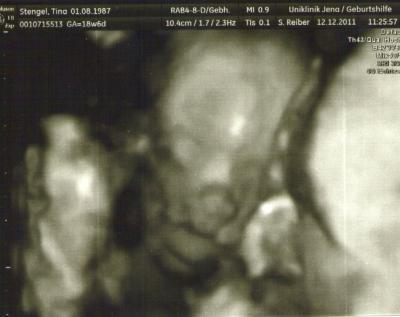

Hey ihr lieben Mai-Mamis, ich hatte ja am Montag die Feindiagnostik und es sind wahnsinns tolle Bilder geworden. Ich lade euch mal eins hoch. Vielleicht erkennt ihr was drauf :-)

Bild zu Bilder feindiagnostik - Forum für Mai - Mamis